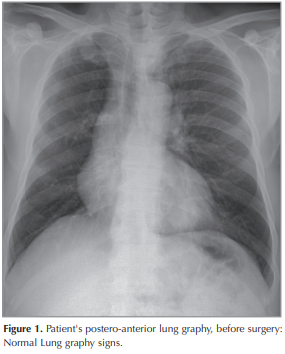

The patient is a 51-year old man, presented with shorthness of breath and cough for 1 months. Chest x-ray was normal (Figure 1). Chest CT scan showed a 30-25 mm heterogeneously enhanced mass lesion with well defined margin, In the left lower lobe of the lung (Figure 2). Bronchoscopy showed no endobronchial lesion. After the PET-CT, the patient was staged as cT2aN1M0 (Stage 2B) (Figure 3). He received video-assisted thoracoscopic surgery of left lower lobe of lung and mediastinal lymph nodes dissection ((Figure 4),(Figure 5)). His Ebv-Dna is Positive in blood tests. The pathology, immunohistochemical staining,and in situ hybridization results confirmed LELC of lung (Figure 6). Using in situ hybridization with exhibition of abundant EBV-encoded small nuclear RNA, in the majority of tumor cells is done. He received 4 cycles of induction chemotherapy with cysplatine and vinoralbine. The patient was discharged from hospital with close follow-up. No recurrence has been detected so far.

The patient is a 51-year old Turkish man, presented with shortness of breath and mild cough for 1 months. He has no chronic disease. Chest x-ray was normal (Figure 1). Chest CT scan showed a 30 × 25 mm heterogeneously enhanced mass lesion with well defined margin and lobulated contour, in the left lower lobe of the lung (Figure 2). Bronchoscopy showed no endobronchial lesion. Head and neck CT scan and nasopharyngeal fiberoscopy were performed and no obvious tumor was found. After the PET-CT, the patient was staged as cT2aN1M0 (Stage 2B), (Figure 3). He received video-assisted thoracoscopic surgery, of left lower lobe of the lung and mediastinal lymph nodes dissection ((Figure 4),(Figure 5)). His Ebv-Dna is Positive in blood tests. The pathology, immunohistochemical staining (Figure 6) and in situ hybridization results confirmed LELC of the lung. Using in situ hybridization with exhibition of abundant EBV-encoded small nuclear RNA, in the majority of tumor cells is done. Immunohistochemical staining was positive for cytokeratin (CK), a marker which was almost always positive in LELC of lung. He was discharged 10 days after the operation. He received 4 cycles of induction chemotherapy with cysplatine and vinoralbine. The patient had no postoperative complication and was discharged with the advice of chemotherapy. No recurrence has been detected so far.